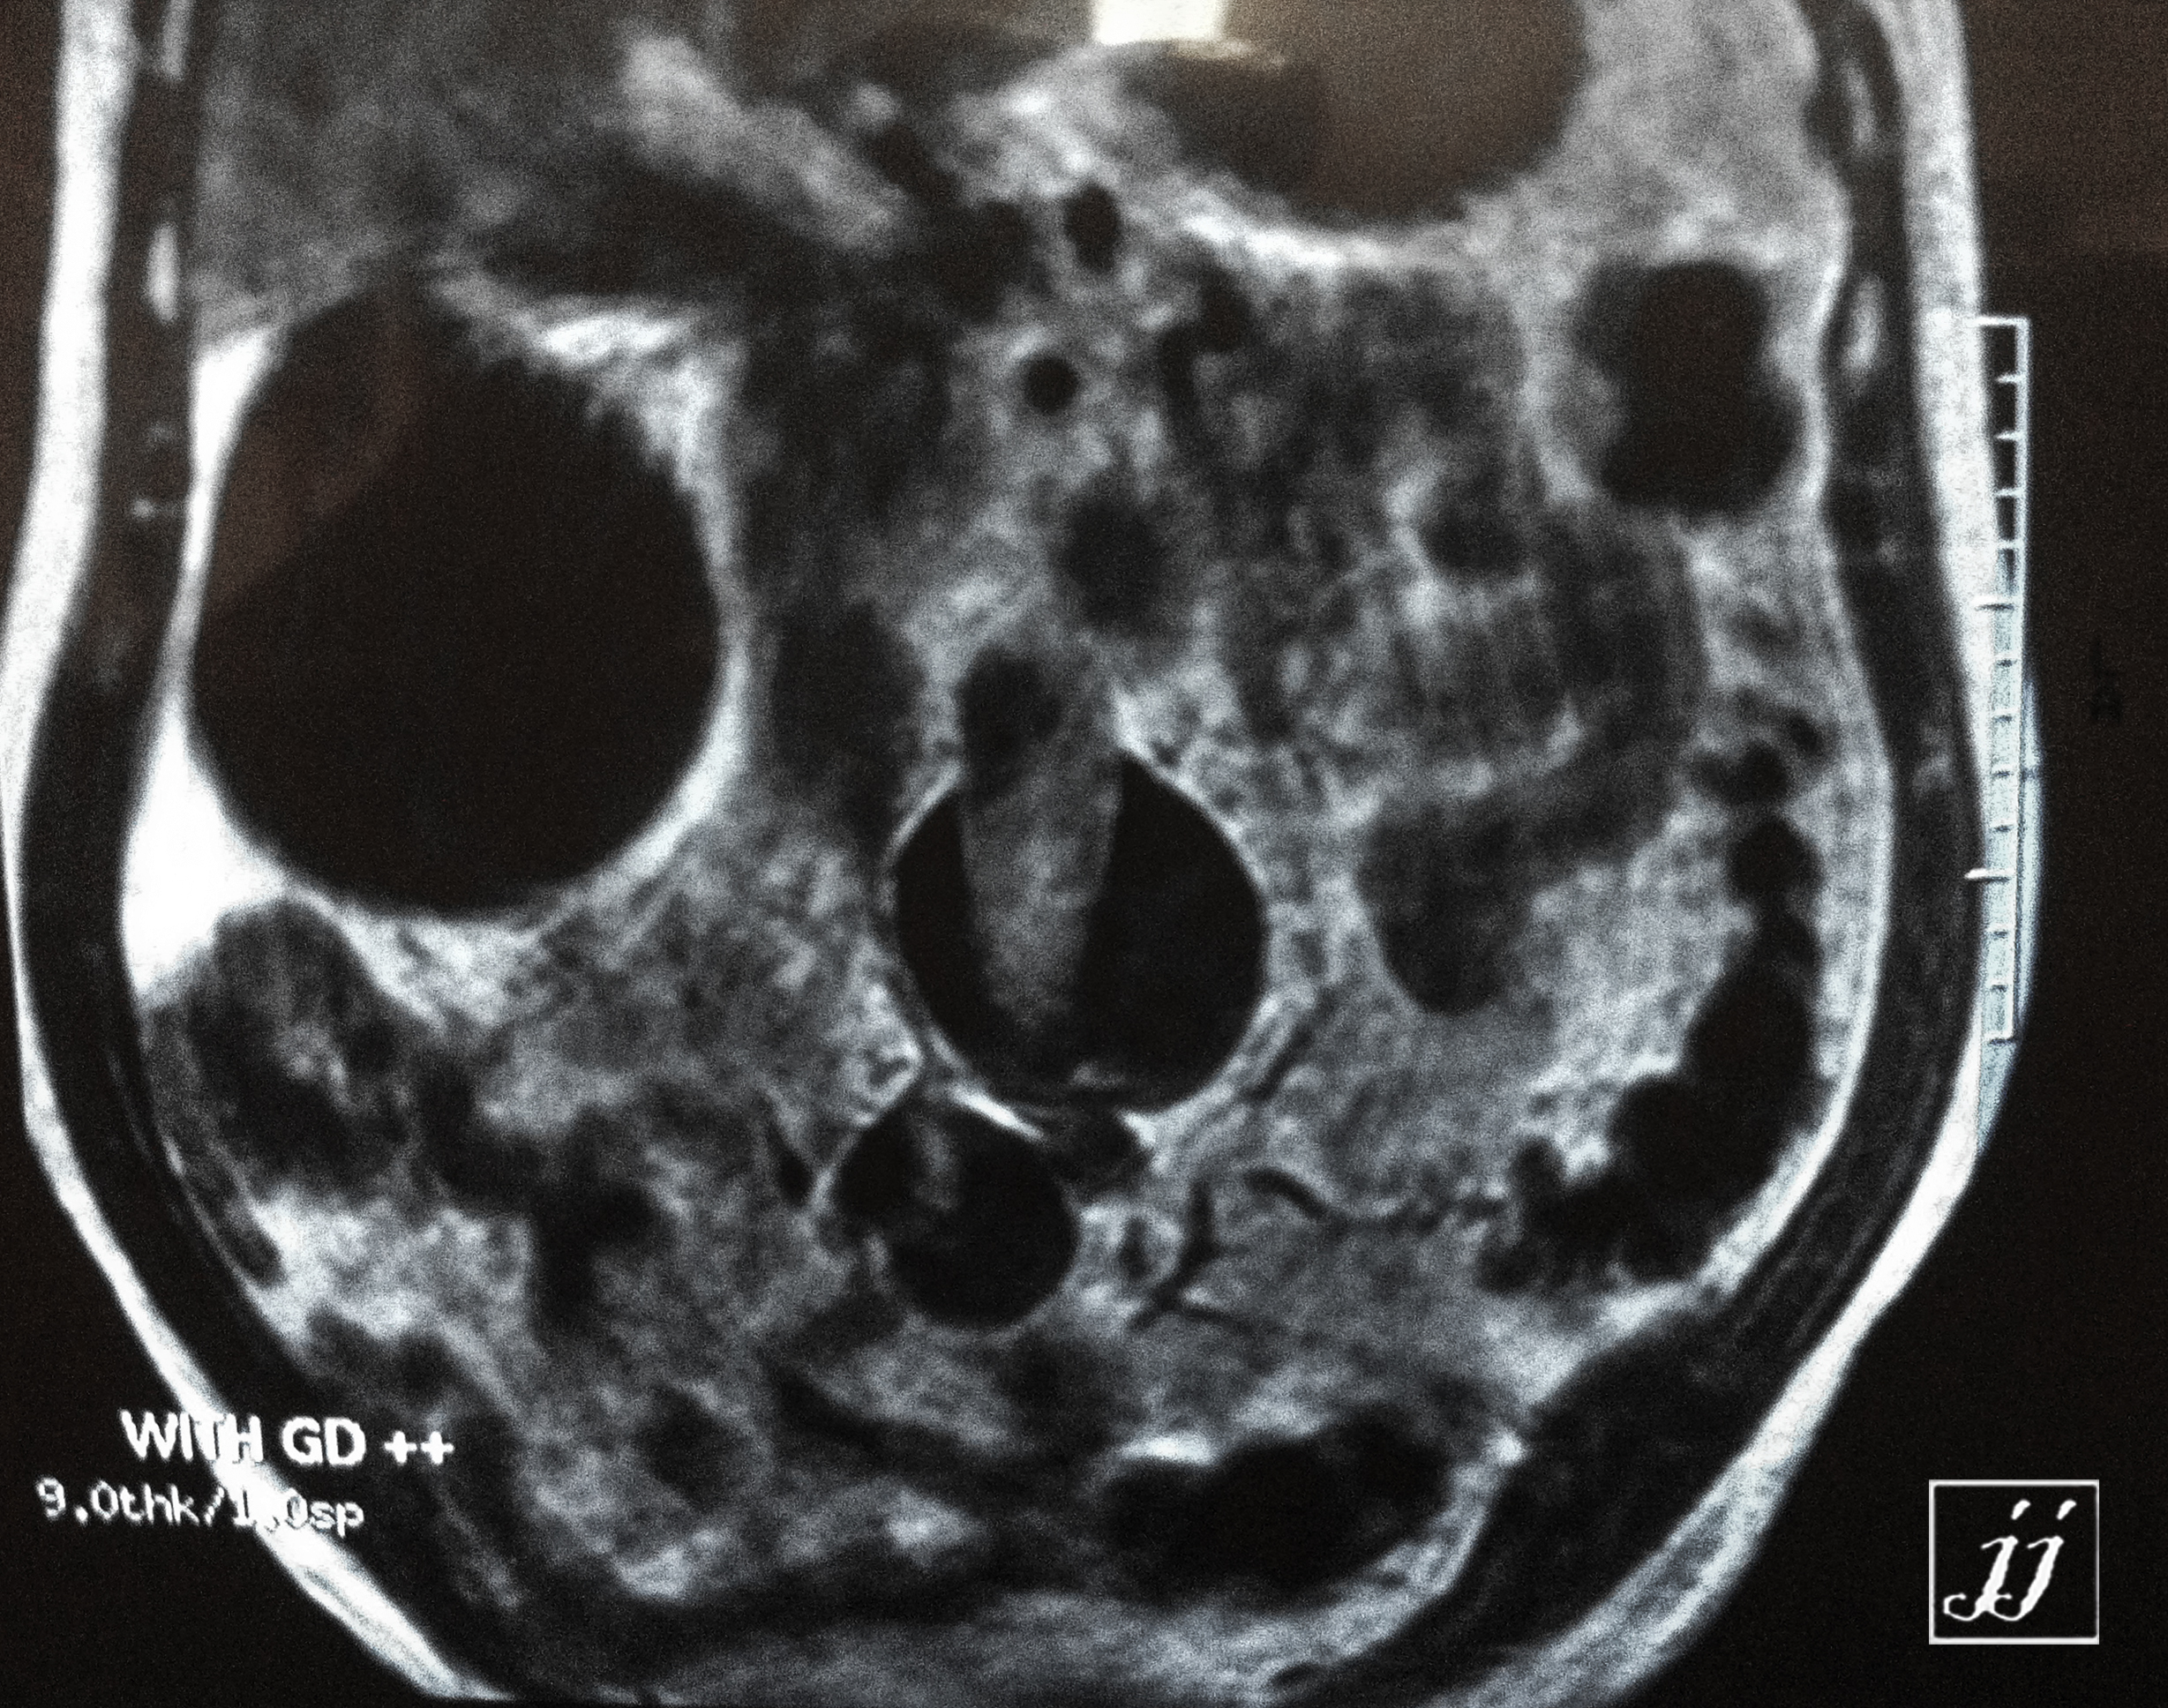

Vascular- Aortic and iliac dissection and aneurysm (5)Patient Data

Vascular- Aortic and iliac dissection and aneurysm (5)Patient Data